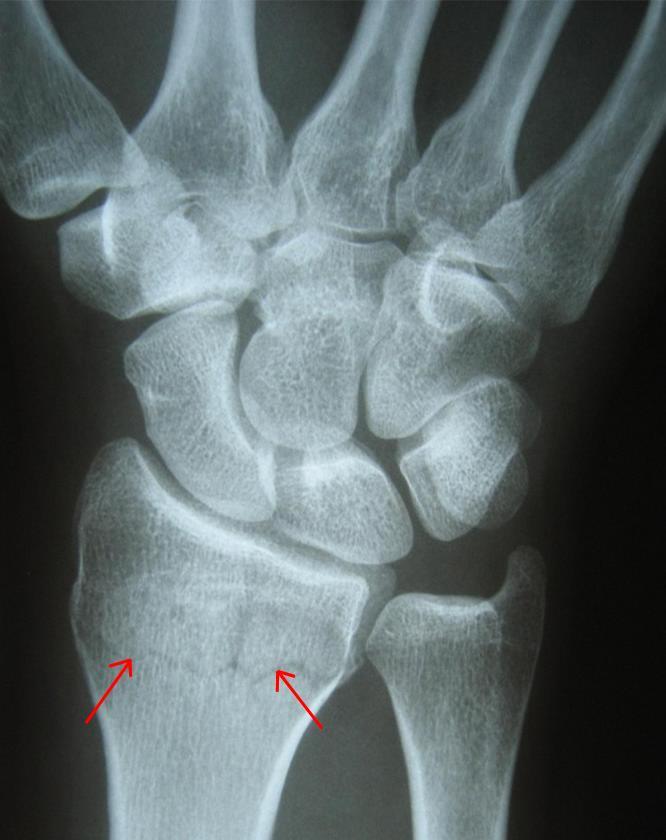

• Оригиналы или надлежащим образом заверенные копии всей медицинской документации обследуемого лица, относящейся к предмету экспертизы (истории болезни, амбулаторные карты, протоколы операций, справки, выписки, результаты всех видов обследований, включая рентгенограммы, КТ/МРТ-снимки, УЗИ-протоколы, лабораторные анализы).

• Параклинические методы исследования: Включают широкий спектр лабораторных и инструментальных исследований, таких как общий и биохимический анализ крови, мочи, рентгенография, компьютерная томография (КТ), магнитно-резонансная томография (МРТ), ультразвуковые исследования (УЗИ), электрокардиография (ЭКГ), электроэнцефалография (ЭЭГ) и другие, в зависимости от предполагаемого характера повреждений или заболеваний.